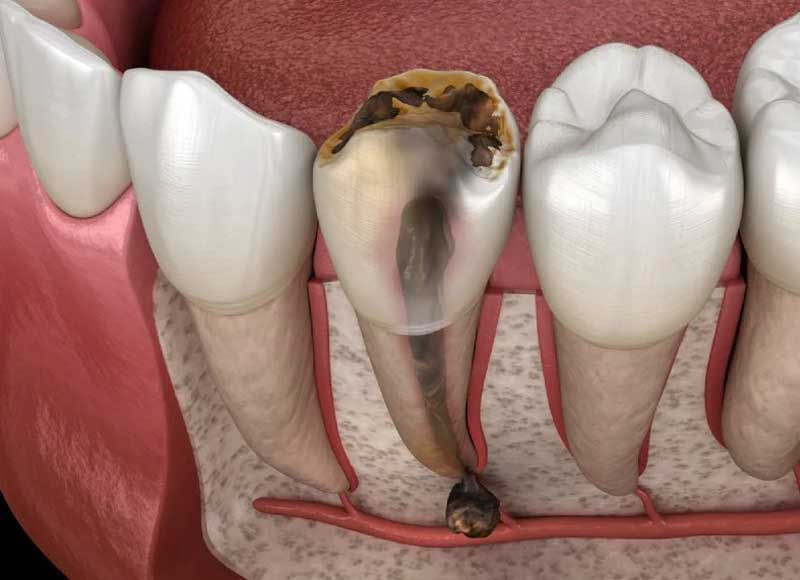

Răng bao gồm 3 lớp chính là men răng, ngà răng và tủy răng. Trong số đó, tủy răng đóng vai trò quan trọng nhất, chịu trách nhiệm về việc truyền dẫn các xung thần kinh và cung cấp dưỡng chất cho răng. Do đó, khi tủy bị tổn thương, sẽ gây ra cảm giác đau đớn và tiềm ẩn nhiều biến chứng nguy hiểm.

Viêm tủy răng có mủ là do tủy răng bị vi khuẩn tấn công, tạo ra sự nhiễm trùng và hình thành một loạt vết viêm xung quanh chân răng. Khi mắc phải tình trạng này, bạn sẽ trải qua cảm giác đau đớn vô cùng khó chịu, bởi tủy răng có nhiều mạch máu và dây thần kinh.

- Sâu răng: Trong trường hợp này, vi khuẩn tấn công và tạo ra các lỗ sâu, xâm nhập qua lớp men răng và ngà răng, lan ra đến tủy răng và gây ra viêm tủy.